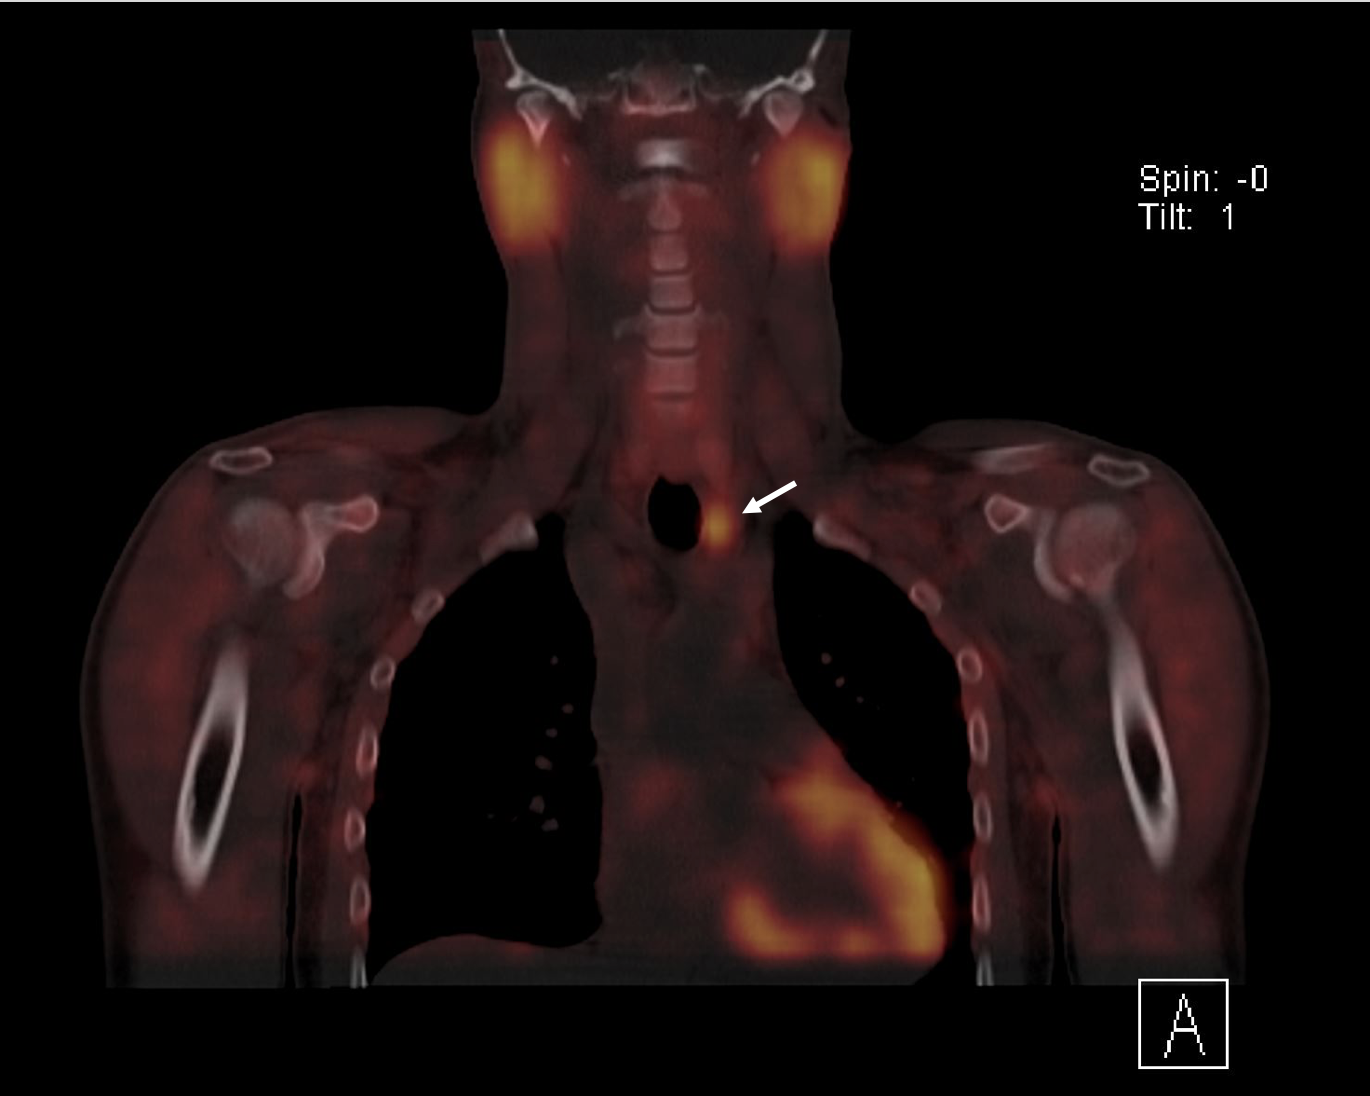

An ultrasound examination of the chest performed using a Toshiba Aplio 500 high-frequency probe showed an acute linear fracture through the anterior cortex of the sternum just below the level of the sternomanubrial joint (FIGURE 1). The subjacent third costal cartilage was unremarkable. A bone densitometry DEXA scan showed osteoporosis of the L2-L4 vertebral bodies with both T-score and Z-scores measuring -2.9 (FIGURE 2). Bone density of the bilateral femora was normal (T score -0.9). Further imaging of the neck was arranged to investigate the cause of the inappropriate parathyroid hormone levels. An ultrasound of the neck revealed a well-defined, hypoechoic nodule located just inferior to the lower pole of the left lobe of the thyroid gland measuring 14x8x5mm (FIGURE 3). The patient then underwent a SPECT-CT of the neck and chest to ensure co-localisation on two imaging modalities. 739 MBq of technetium 99m was injected and acquisitions were obtained at 10min, 90mins and 180mins following tracer injection. Analysis of the SPECT data demonstrated a well-defined area of retained activity situated in the lower pole of the left lobe of the thyroid which correlated well with the findings of the ultrasound scan (FIGURE 4). The overall appearances were in keeping with a parathyroid adenoma situated in the lower pole of the left lobe of the thyroid. The CT component of the study also showed a further view of the fracture (FIGURE 5).